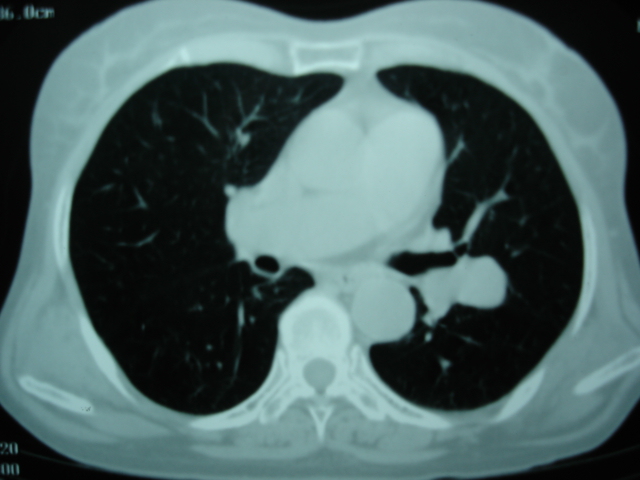

以下是引用卜一在2009-9-7 19:51:00的发言:[br][br] 1 左侧胸内甲状腺占位-多考虑甲状腺腺瘤! 2、左肺门占位-建议增强扫描以便明确性质。 3 慢支并感染! [br]

以下是引用shibing在2009-9-7 20:40:00的发言:[br]左侧胸内甲状腺占位-多考虑甲状腺腺瘤! 2、左肺门占位-建议增强扫描以便明确性质。 3 慢支并感染! [br]